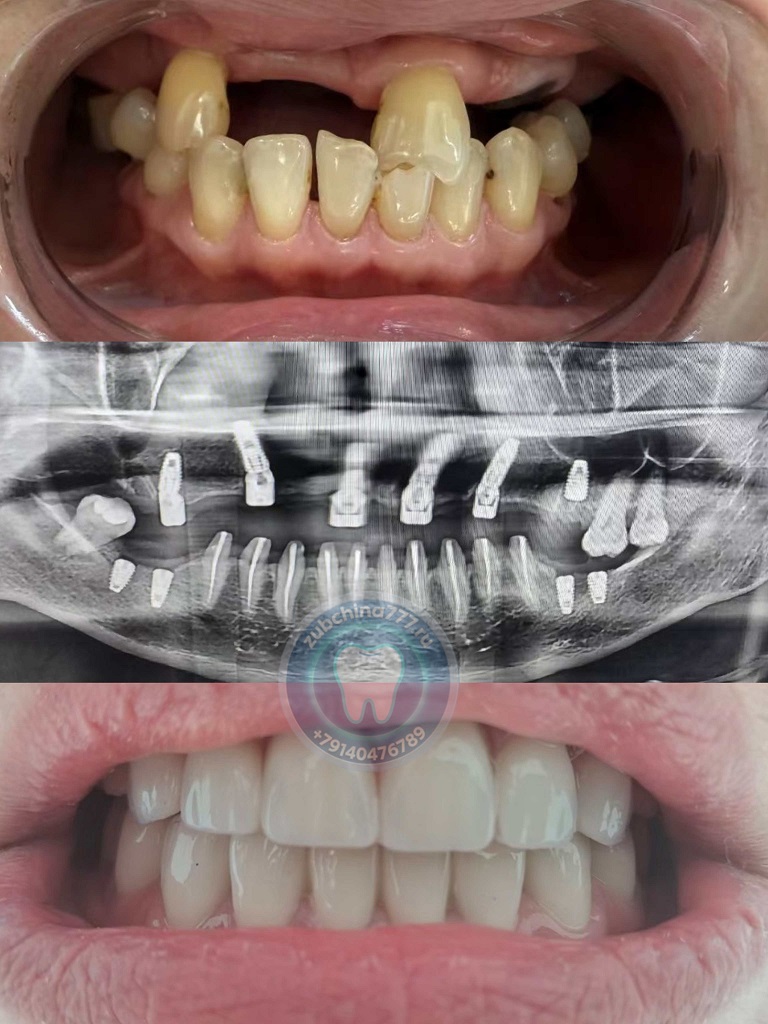

Фотографии пациентов ДО и ПОСЛЕ лечения и протезирования зубов в Хэйхэ